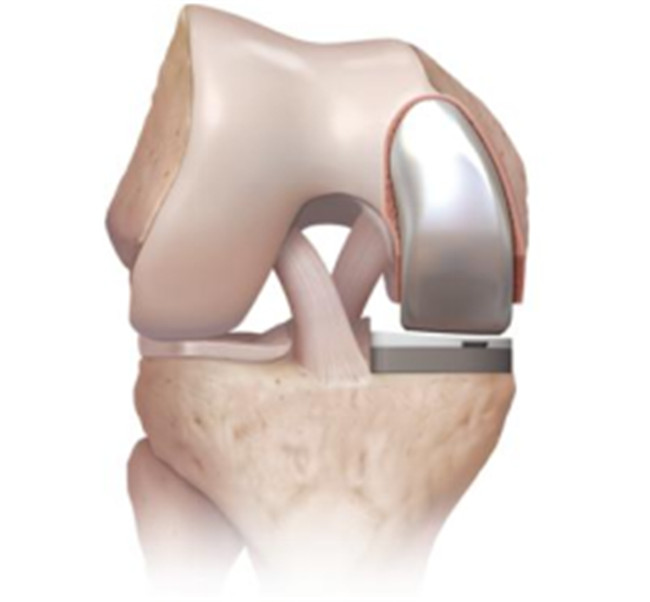

對(duì)于全膝關(guān)節(jié)置換術(shù)而言,膝關(guān)節(jié)單髁置換術(shù)是相對(duì)微創(chuàng)手術(shù),精準(zhǔn)置換病損部位,用以替代膝關(guān)節(jié)股、脛關(guān)節(jié)損壞的軟骨表面和半月板,被稱(chēng)為膝關(guān)節(jié)置換中的“補(bǔ)牙技術(shù)”,不需要去除前后交叉韌帶,最大限度保留病人的本體感覺(jué)和關(guān)節(jié)功能,實(shí)現(xiàn)膝關(guān)節(jié)置換手術(shù)的生理性重建。膝關(guān)節(jié)單髁置換手術(shù)具有損傷小、術(shù)后恢復(fù)快、手術(shù)外表美觀和住院時(shí)間短等優(yōu)點(diǎn),是治療膝關(guān)節(jié)骨關(guān)節(jié)炎的理想辦法。目前,單髁置換技術(shù)是關(guān)節(jié)外科發(fā)展方向之一,隨著手術(shù)器械的發(fā)展和認(rèn)識(shí)水平的提高,單髁置換術(shù)在臨床將會(huì)擁有廣泛的應(yīng)用前景。

羅軍主任表示:膝關(guān)節(jié)單髁置換術(shù)(unicompartmental kneearthroplasty, UKA)是相對(duì)全膝關(guān)節(jié)置換術(shù)而言的一種新型微創(chuàng)手術(shù),切口僅為原來(lái)的一半,且能最大限度地保留患者正常的關(guān)節(jié)部分,對(duì)患者的損傷更小,術(shù)后療效更佳,是骨性關(guān)節(jié)炎患者的一大福音。